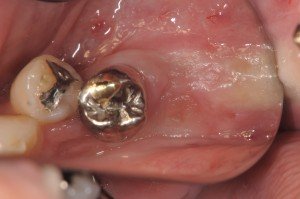

今日のオペは、左下6番部位にスプライン5.0Φ×8mmを通常埋入しました。

6番が歯根破折で、近心根相当部に骨欠損が残っていたので、やや遠心に埋入となっています。

6番部位にスプライン埋入したところです。

7番は同時に2次オペ、6番は1回法で通常埋入です。